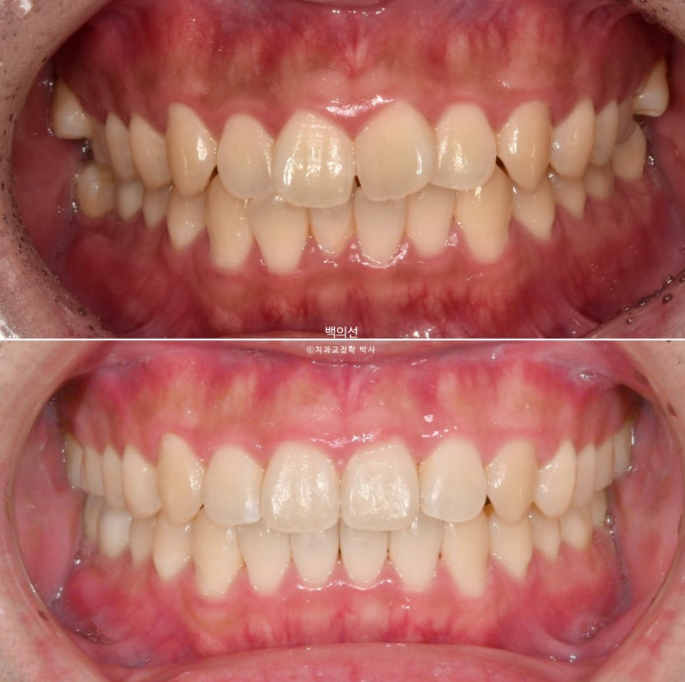

치료 전 후 비교해보겠습니다.

좌 치료 전 / 우 치료 후

24.01~25.05

총 치료기간은 1년 4개월이며 인비절라인으로 치료한 기간은 9개월 입니다.

앞니 돌출의 개선

깔끔해진 미소가 돋보이네요.